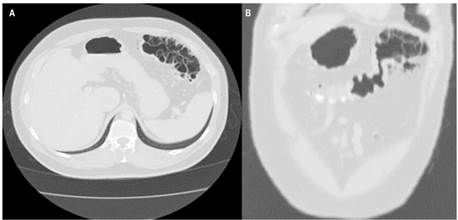

Se trata de un paciente masculino de 35 años de edad que consultó por un cuadro clínico de un mes de evolución de dolor de alta intensidad, inespecífico, localizado en el hemiabdomen inferior, con irradiación a la región lumbar derecha, sin desarrollo clínico de abdomen agudo. Tuvo un diagnóstico inicial de infección de las vías urinarias y tratamiento con levofloxacina ambulatoriamente, pero ante la no mejoría de los síntomas, el paciente volvió a consultar. Se realizó una tomografía axial computarizada (TAC) contrastada de abdomen, en la que se evidenció una neumatosis intestinal quística segmentaria en el ángulo esplénico del colon asociado con áreas de neumoperitoneo adyacentes (Figura 1). Fue valorado por el servicio de cirugía general, en el que se inició el manejo con laparoscopia y se encontró plastrón con epiplón y neumatosis en el ángulo esplénico, por lo que convierten el procedimiento inicial a una laparotomía, en la que decidieron realizar hemicolectomía izquierda, omentectomía parcial y colostomía izquierda.

Figura 1 TAC con evidencia de neumatosis intestinal quística en el ángulo esplénico del colon, asociada con múltiples burbujas de neumoperitoneo. A. Corte axial. B. Corte coronal.